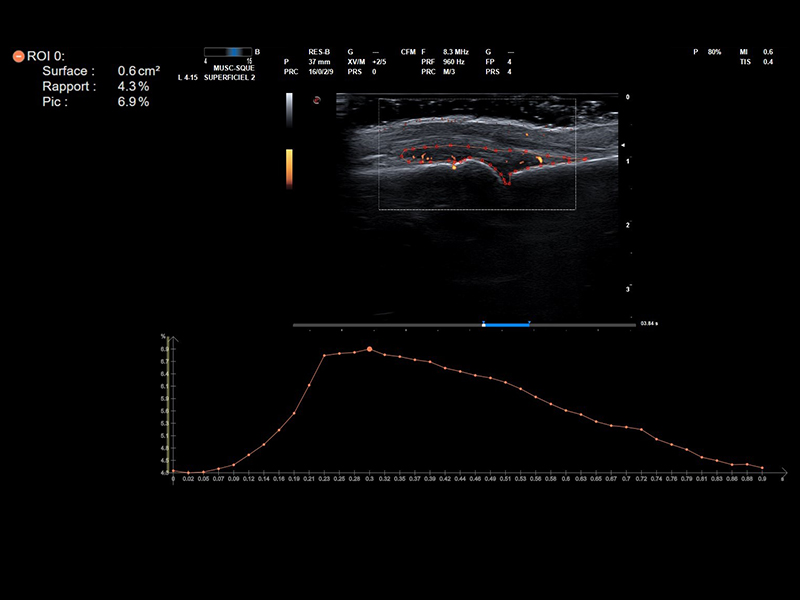

Doppler technology, frequently employed in the assessment of inflammatory conditions, especially in the field of rheumatology, is a non-invasive imaging technique that measures blood flow and can be particularly informative in the context of synovial inflammation.

Esaote Power Doppler, achieving a very high level of sensitivity, and microV, which is a step ahead in the visualization of micro vascularization, deliver high quality Doppler information that the clinician can rely on, while QPack Esaote Technology enables a quantitative assessment of the inflammatory area.

Follow-up in rheumatology plays a pivotal role in the effective management of rheumatic diseases by monitoring disease progression and piloting the therapy. The Follow Up & Multimodality tool developed by Esaote allows a comparison between real-time US and a second ultrasound image or a second modality image.

This technology can be used together with the QPack one, as it is crucial for rheumatologists to assess and quantify how the level of flows change over time in the same target areas.